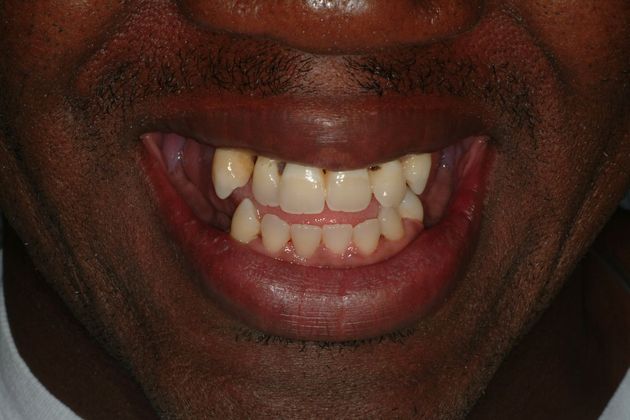

This young man had an early onset of periodontal disease (gum disease) causing him to have all loose upper teeth and loose lower back teeth, all of which needed to be removed. After that, 6 implants were placed in the upper jaw for the All-on-6 bridge and 4 implants were placed in the lower jaw for bridges for back side of the mouth. The lower front natural teeth were cleaned off disease and maintained.

Procedures : extractions, implants, All on 6, Teeth in a day, bite correction.